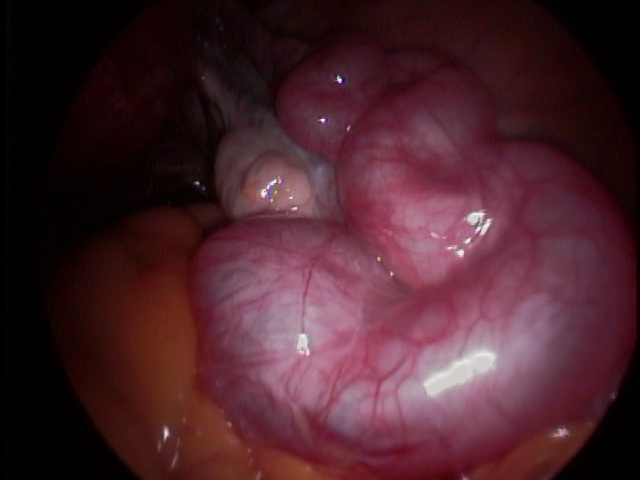

Ooforoplastia é a técnica em que se remove o cisto do ovário, preservando o restante do mesmo. Indicado para mulheres em idade fértil, que desejam a preservação da fertilidade.

Ooforectomia é a remoção do ovário. Indicada nos cistos de ovários em pacientes que já estão na menopausa, nos casos de câncer de ovário, entre outros.